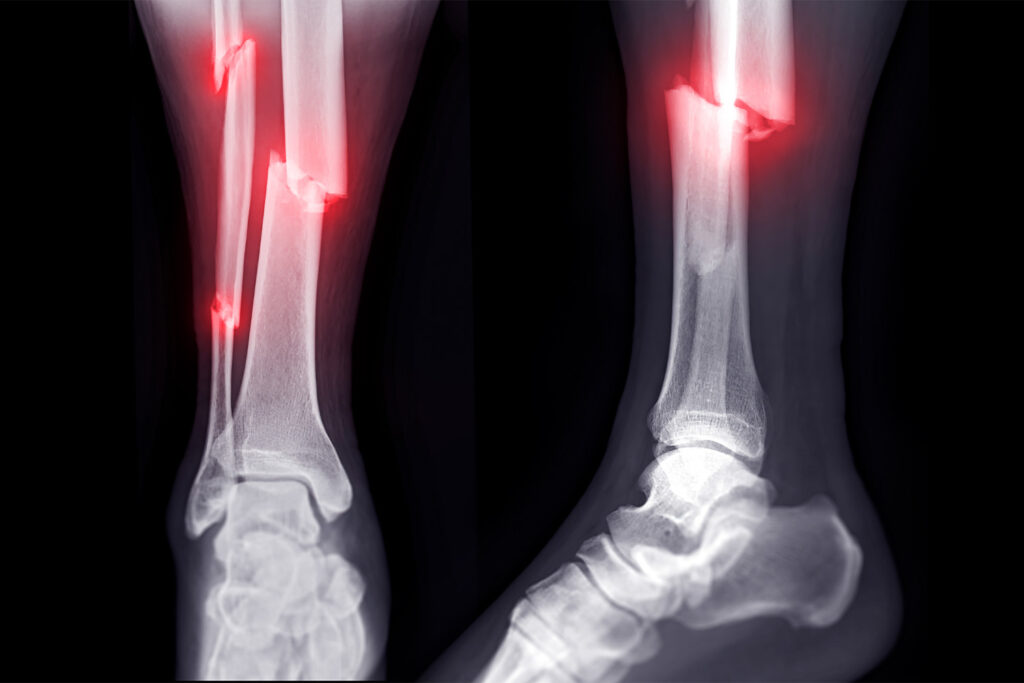

Fracture

Fracture Treatment in Banashankari